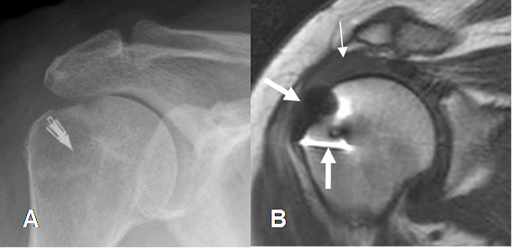

Fig 160. Cambios PostQx.

A: Rx AP. Material Qx por reconstrucción del manguito rotador.

B: RM coronal en T2. Reconstrucción de lesión del manguito, con un tendón del supraespinoso engrosado e hiperintenso, por tendinitis crónica. (Flecha delgada). Se aprecian artefactos metálicos. (Flecha gruesa).